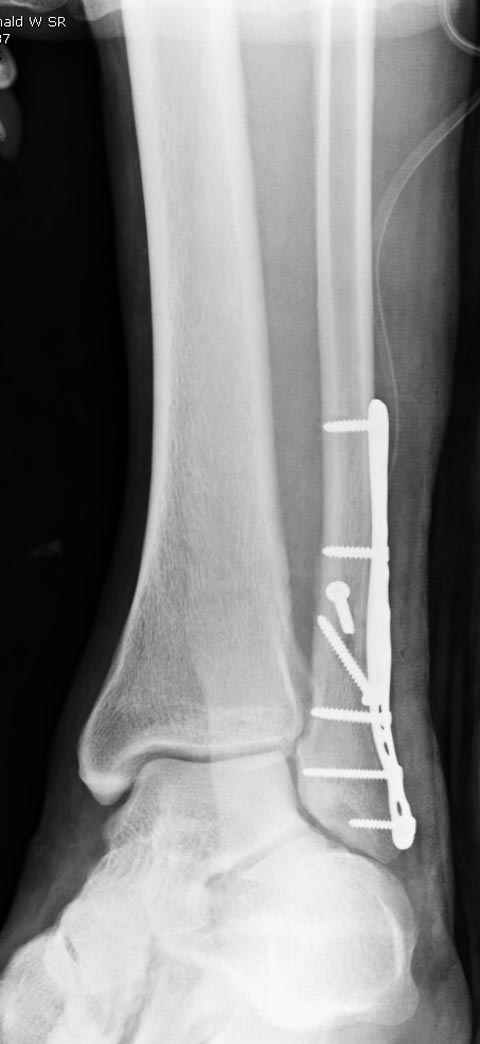

Тему неоднократно разбирали (см. архив), как всегда, недостаточны ренгенологические исследования - кроме прямого и боковых снимков, еще нужна косая ренгенограмма для определения ankle mortise, без мортиз снимка трудно определить высоту и ротацию малоберцовой. (снимки)

Показания для фиксации: укорочения и ротация малоберцовой, особенно обращают внимание на любой подвывих таранной кости: неустраненый подвывих впоследствии приводит к раннему артрозу. Задний край фиксирует тогда, когда перелом составляет около 25% суставной поверхности голеностопного сочленения и смещение более 2мм.

По снимку ваш случай относится к Weber В, фиксацию производят восстановлением длины малоберцовой кости, под ренгеном (ЭП)контролем, для этого я предпочел бы латеральный доступ, остеотомия по линии перелома, удлинение малоберцовой засчет скоса линии остеотомии, компрессия “lag technique”по линии остеотомии и фиксацию провести латеральной пластиной. Отдельный задний доступ, остеотомия по линии перелома, репозиция и фиксация заднего края вашим предпочтительным методом: 3.5мм шурупом с шайбой или пластиной Antiglide Butress

method. При восстановленном суставе, уменьшится медиальная щель, а при Weber В повреждается только передне-нижняя межберцовая связка синдесмоза, повреждение которой приводит к наружной ротации

малоберцовой, но после восстановления всех смещений, связка автоматический приближается к исходному и нет необходимости восстановления синдесмоза.